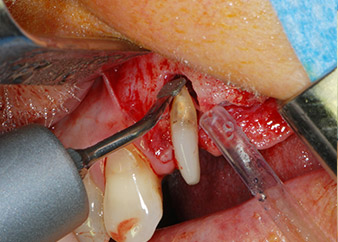

Vor der Insertion der Implantate wurde infiziertes Weichgewebe im Implantationsbereich und um das Abutment mit einem Instrument entfernt, das laut Hersteller primär zur Knochenbearbeitung und zum Sammeln von Knochenspänen vorgesehen ist (Piezomed, Einsatz B5) (Abb. 6 und 7).

piezochirurgisches Instrument

Abb. 6: Der Operationsbereich wird dann mit einem schabenden piezochirurgischen Instrument gereinigt.

Knochendefizite

Abb. 7: Nach dem Debridement sind die Knochendefizite an Zahn 27 mesial und um die Wurzel von Zahn 24 deutlich sichtbar.

Im folgenden Schritt wurde das jeweilige Implantatbett an den Positionen 25 und 26 mit rotierenden Instrumenten in einem Winkelstück mit einem Übersetzungsverhältnis von 20:1 (WS-75 L G, W&H) und einem vor Kurzem aktualisierten leistungsstarken Implantatmotor präpariert (Implantmed, W&H) (Abb. 8 und 19).

Die Abschlusspräparation am Sinus erfolgte wieder mit einem piezochirurgischen Instrument.

Vor der Insertion der Implantate und nach Überprüfung der intakten Schneiderschen Membran (Abb.9) wurde der interne Sinusboden an beiden Implantatpositionen mittels eines xenogenen Knochenersatzmaterials (Abb. 10) augmentiert.